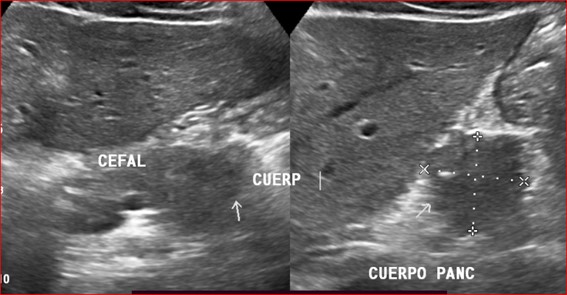

Caso 4

Paciente masculino de 35 años de edad, con antecedentes de tabaquismo, etilismo, consumo de sustancias psicoactivas. Ingresa al hospital de Sanatorio Franchin el 24 de mayo de 2024, donde se constata hipoglucemia severa con buena respuesta al glucosado hipertónico endovenoso. Al examen físico con la típica tríada de Whipple, dado por síntomas neuroglucopénicos de alteración del estado de conciencia, glucemia de 25 mg/dl y alivio sintomático después de la administración de glucosa. El paciente recupera el estado de conciencia y refiere dolor abdominal a nivel de epigastrio, por lo que se le realiza ecografía abdominal, donde se evidencia lesión nodular hipoecogénica en cuerpo del páncreas. Por esta razón se pasa al paciente a tomografía, donde se constata una formación nodular a nivel del cuerpo del páncreas, que presenta un ávido realce en fase arterial con homogeneización de la lesión en tiempo tardío.